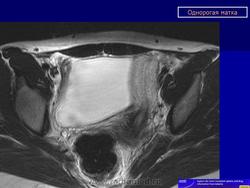

МПС. Женская репродуктивная система. Аномалии и варианты развития. Матка. Однорогая матка. +

Аномалии и варианты развития. Однорогая матка.